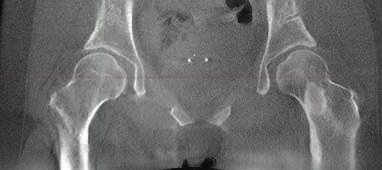

Nancy Antone, 72, is one of our grateful Campbell Clinic trauma patients. She was working in her yard when she fell in late 2022, breaking the top of her right femur. During the next year, she underwent five surgeries—once to implant a metal rod, once to address an E.coli infection, a third operation to replace the incorrectly situated rod with an antibiotic one, a fourth operation to implant an all-new metal rod, then finally a knee replacement. After her original operation at Baptist-Desoto, Ms. Antone consulted with Dr. Marc Mihalko, then was under the care of Drs. Cosgrove and Gregory Dabov.